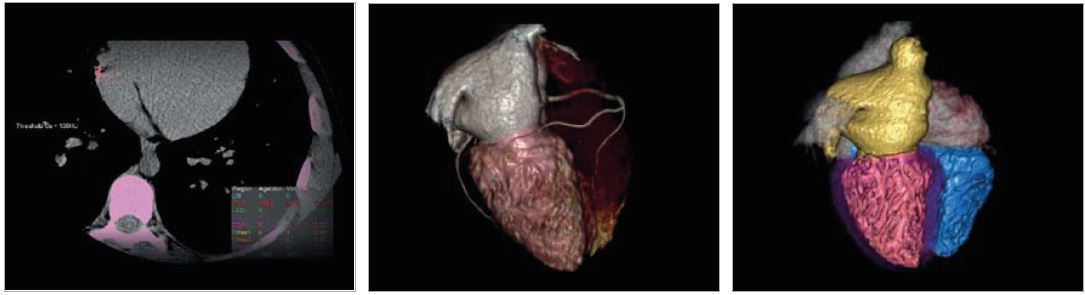

• Перетворювати медичні зображення в 3D моделі для широкого спектру застосувань від навчання пацієнтів до планування складних інтервенційних втручань

Vitrea Advanced Visualization — це мультимодальна платформа перегляду, яка забезпечує широкий діапазон функцій із можливістю додавання ще більше функцій, коли це потрібно. Ми пропонуємо комплексні набори інструментів, які надають лікарям інформацію для планування процедур і діагностики пацієнтів.

Vitrea — це мультимодальне рішення. Наш набір передових програм надає повноцінні рішення для розширеної20,3D і 4D візуалізації, які використовуються для обробки та аналізу клінічних даних з різних модальностей - MPT, КТ, CR, DX, RG, RF, УЗД, ХА, NM, ПЕТ,ПЕТ/КТта ОФЕКТ.